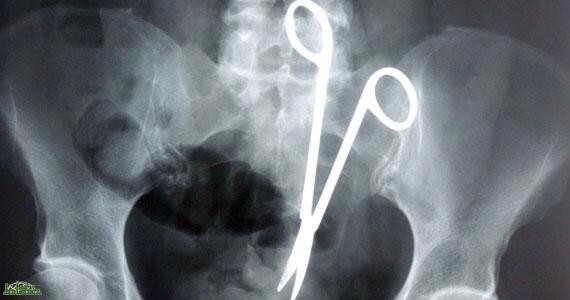

رجل من البوسنة يكتشف وجود مقص داخل معدته سبب له آلام كثيرة لمدة9سنوات حيث أجرى عملية سابقة ونسي الأطباء المقص بمعدته